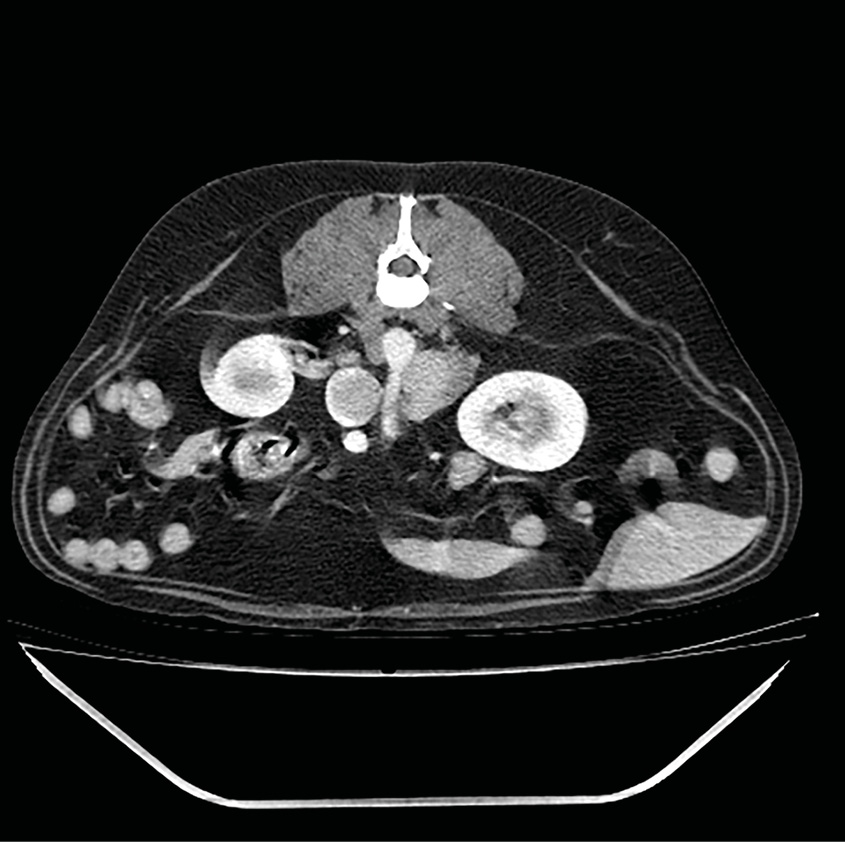

A nivel ecográfico, en perros que padecen hiperadrenocorticismo (síndrome de Cushing) generalmente se observa un aumento de tamaño de las glándulas adrenales. Este incremento es simétrico en caso de hiperadrenocorticismo de origen hipofisiario, mientras que los perros con hiperadrenocorticismo adrenal presentan una masa adrenal unilateral (imagen 2) y la glándula contralateral se identifica disminuida de tamaño o normal18.

El diagnóstico diferencial de nódulos y masas adrenales incluye hiperplasia adrenal, adenoma, adenocarcinoma, feocromocitoma y, con menor frecuencia, aunque también se han reportado: neuroblastoma, ganglioneuroma, mielolipoma, metástasis, granuloma, hematoma21. Ecográficamente no se puede diferenciar un tumor maligno de uno benigno, pero la presencia de una masa igual o superior a 2 cm de tamaño y/o la observación de invasión vascular deben considerarse criterios de malignidad22 (imágenes 3 y 4).